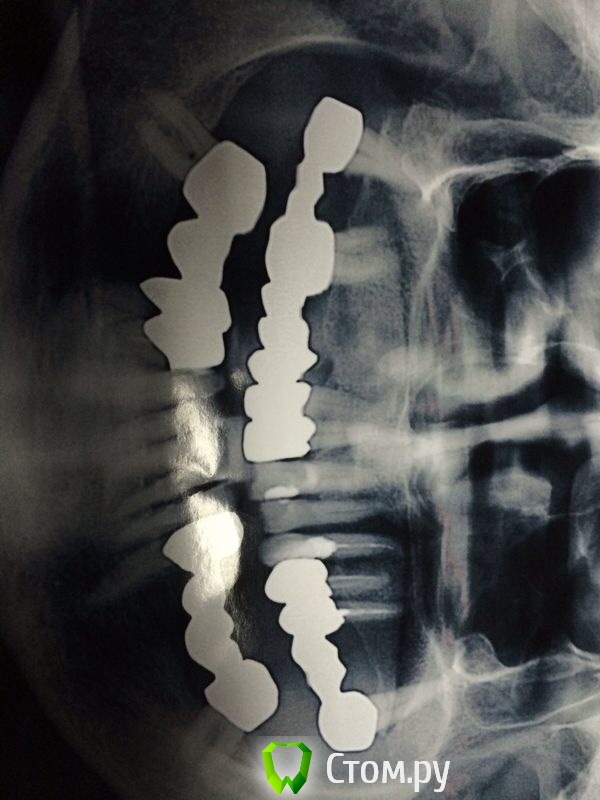

Ислам07 Опубликовано 18 мая, 2014 Поделиться Опубликовано 18 мая, 2014 Уважаемые коллеги подскажите пожалуйста план лечения, меня смущают клиновидные дефекты. Заранее спасибо Ссылка на комментарий

Чертков Александр Опубликовано 19 мая, 2014 Поделиться Опубликовано 19 мая, 2014 Мостовидные скорее всегоВнизу мостовидные - не вариант, долго "ходить" не будут. Для имплантации требуется подготовка (довольно серьёзная). Если пациент не мотивирован на длительное и дорогостоящее лечение - лучше сделать хороший съемный (бюгель на кламмерах)...впрочем и на в\ч тоже. Ссылка на комментарий

chernov Опубликовано 19 мая, 2014 Поделиться Опубликовано 19 мая, 2014 Уважаемые коллеги подскажите пожалуйста план лечения, меня смущают клиновидные дефекты.Клиновидные дефекты(абфракции)признак перегрузки зубов,т.е. о мостовидных протезах (без имплантации) лучше не задумываться-себе дороже. Ссылка на комментарий